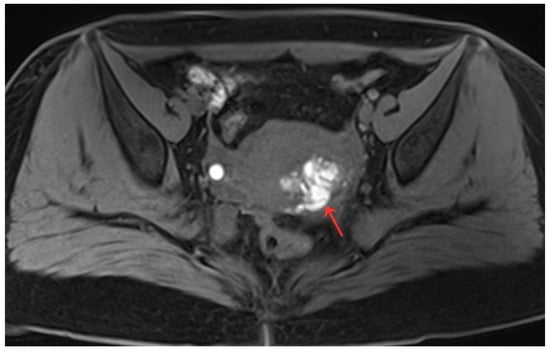

Figure 3.

(a,b) Pelvic MRI shows lesions after HIFU treatment (1st month)(red arrows).